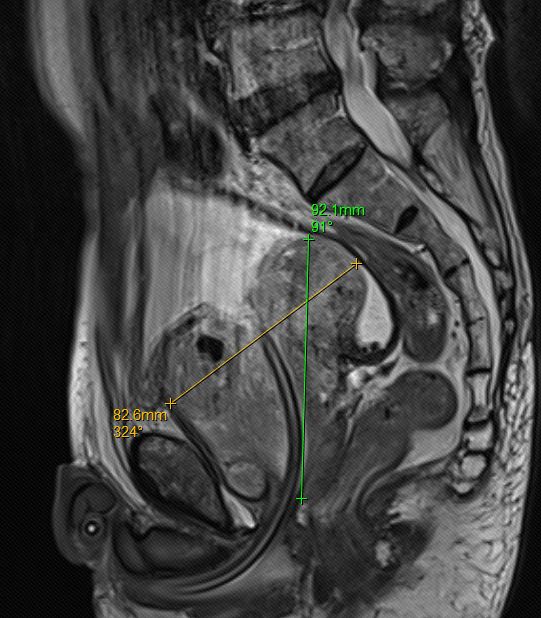

近日,我科完成一例机器人辅助腹腔镜下巨大前列腺根治性切除术。患者为75岁男性,半年前因PSA异常升高(115ng/ml)来院就诊,检查盆腔增强MRI提示前列腺增生(约237ml,为正常前列腺大小10倍左右)、前列腺外周带异常信号考虑前列腺癌可能,PI-RADS评分5分(预示前列腺癌80%可能),予行前列腺穿刺活检,病理确诊前列腺腺癌,Gleason评分5+5=10分。诊断明确,存在手术指征,因患者前列腺体积大,手术难度大,遂行内分泌治疗半年,复查MRI提示前列腺体积明显缩小(约143ml,仍为正常前列腺大小的6-7倍),近日全麻下行机器人辅助腹腔镜下前列腺根治性切除术,术中发现患者前列腺三叶增大,明显突入膀胱,手术过程顺利,术后第二天下床活动,术后第四天带尿管顺利出院。

前列腺矢状面(内分泌治疗前的前列腺大小)